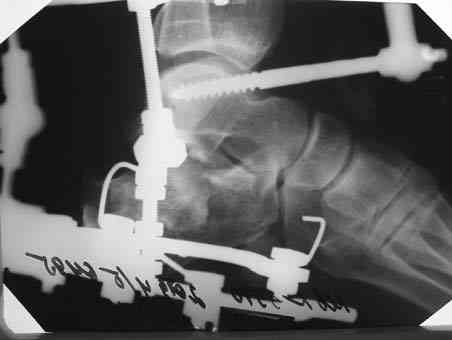

Уважаеемый коллега.Слева ситуация достаточно не сложная.Суставной фрагмент вклинился в тело.Необходимо наружным доступом освободить отломки,поднять суставной фрагмент и фиксировать пяточной пластиной LCP.

Результат посылаю отдельно.На предыдущих рент. видна репозиция.

Справа ситуация сложнее так как имеется помимо перелома имеется вывих тела пяточной костиПоэтому даже если удастся достигнуть хорошей репозиции необходимо сделать первичный подтаранный артродез.Иначе кость не будет держать в своём ложе.Но пластина нужна обязательно чтобы восстановить форму пятки.С уважением Дрягин